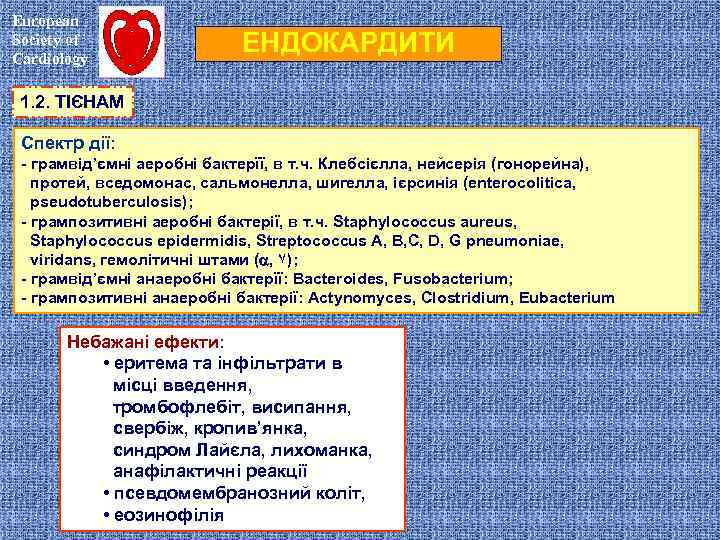

European Society of Cardiology ЕНДОКАРДИТИ ЦЕФАЛОСПОРИНИ мають високу спорідненість до пеніцилін-зв'язуючого білка – 3, що стримує розмноження бактеріальних клітин. Це веде до утворення довгих нитковидних структур (філаментів), збільшення біомаси і продукції ендотоксину. Ендотоксиновий шок. ІМІПІНЕМ (ТІЄНАМ) і йому подібні володіють високою спорідненістю до пеніцилін-зв'язуючого білка-2, який сприяє перетворенню бактерій в сферопласти, що не супроводжується значним руйнуванням клітинної стінки і вивільненням ендотоксину

European Society of Cardiology ЕНДОКАРДИТИ 1. 2. ТІЄНАМ Спектр дії: - грамвід’ємні аеробні бактерїї, в т. ч. Клебсієлла, нейсерія (гонорейна), протей, вседомонас, сальмонелла, шигелла, ієрсинія (enterocolitica, pseudotuberculosis); - грампозитивні аеробні бактерії, в т. ч. Staphylococcus aureus, Staphylococcus epidermidis, Streptococcus A, B, C, D, G pneumoniae, viridans, гемолітичні штами ( , ۷); - грамвід’ємні анаеробні бактерїї: Bacteroides, Fusobacterium; - грампозитивні анаеробні бактерії: Actynomyces, Clostridium, Eubacterium Небажані ефекти: • еритема та інфільтрати в місці введення, тромбофлебіт, висипання, свербіж, кропив’янка, синдром Лайєла, лихоманка, анафілактичні реакції • псевдомембранозний коліт, • еозинофілія